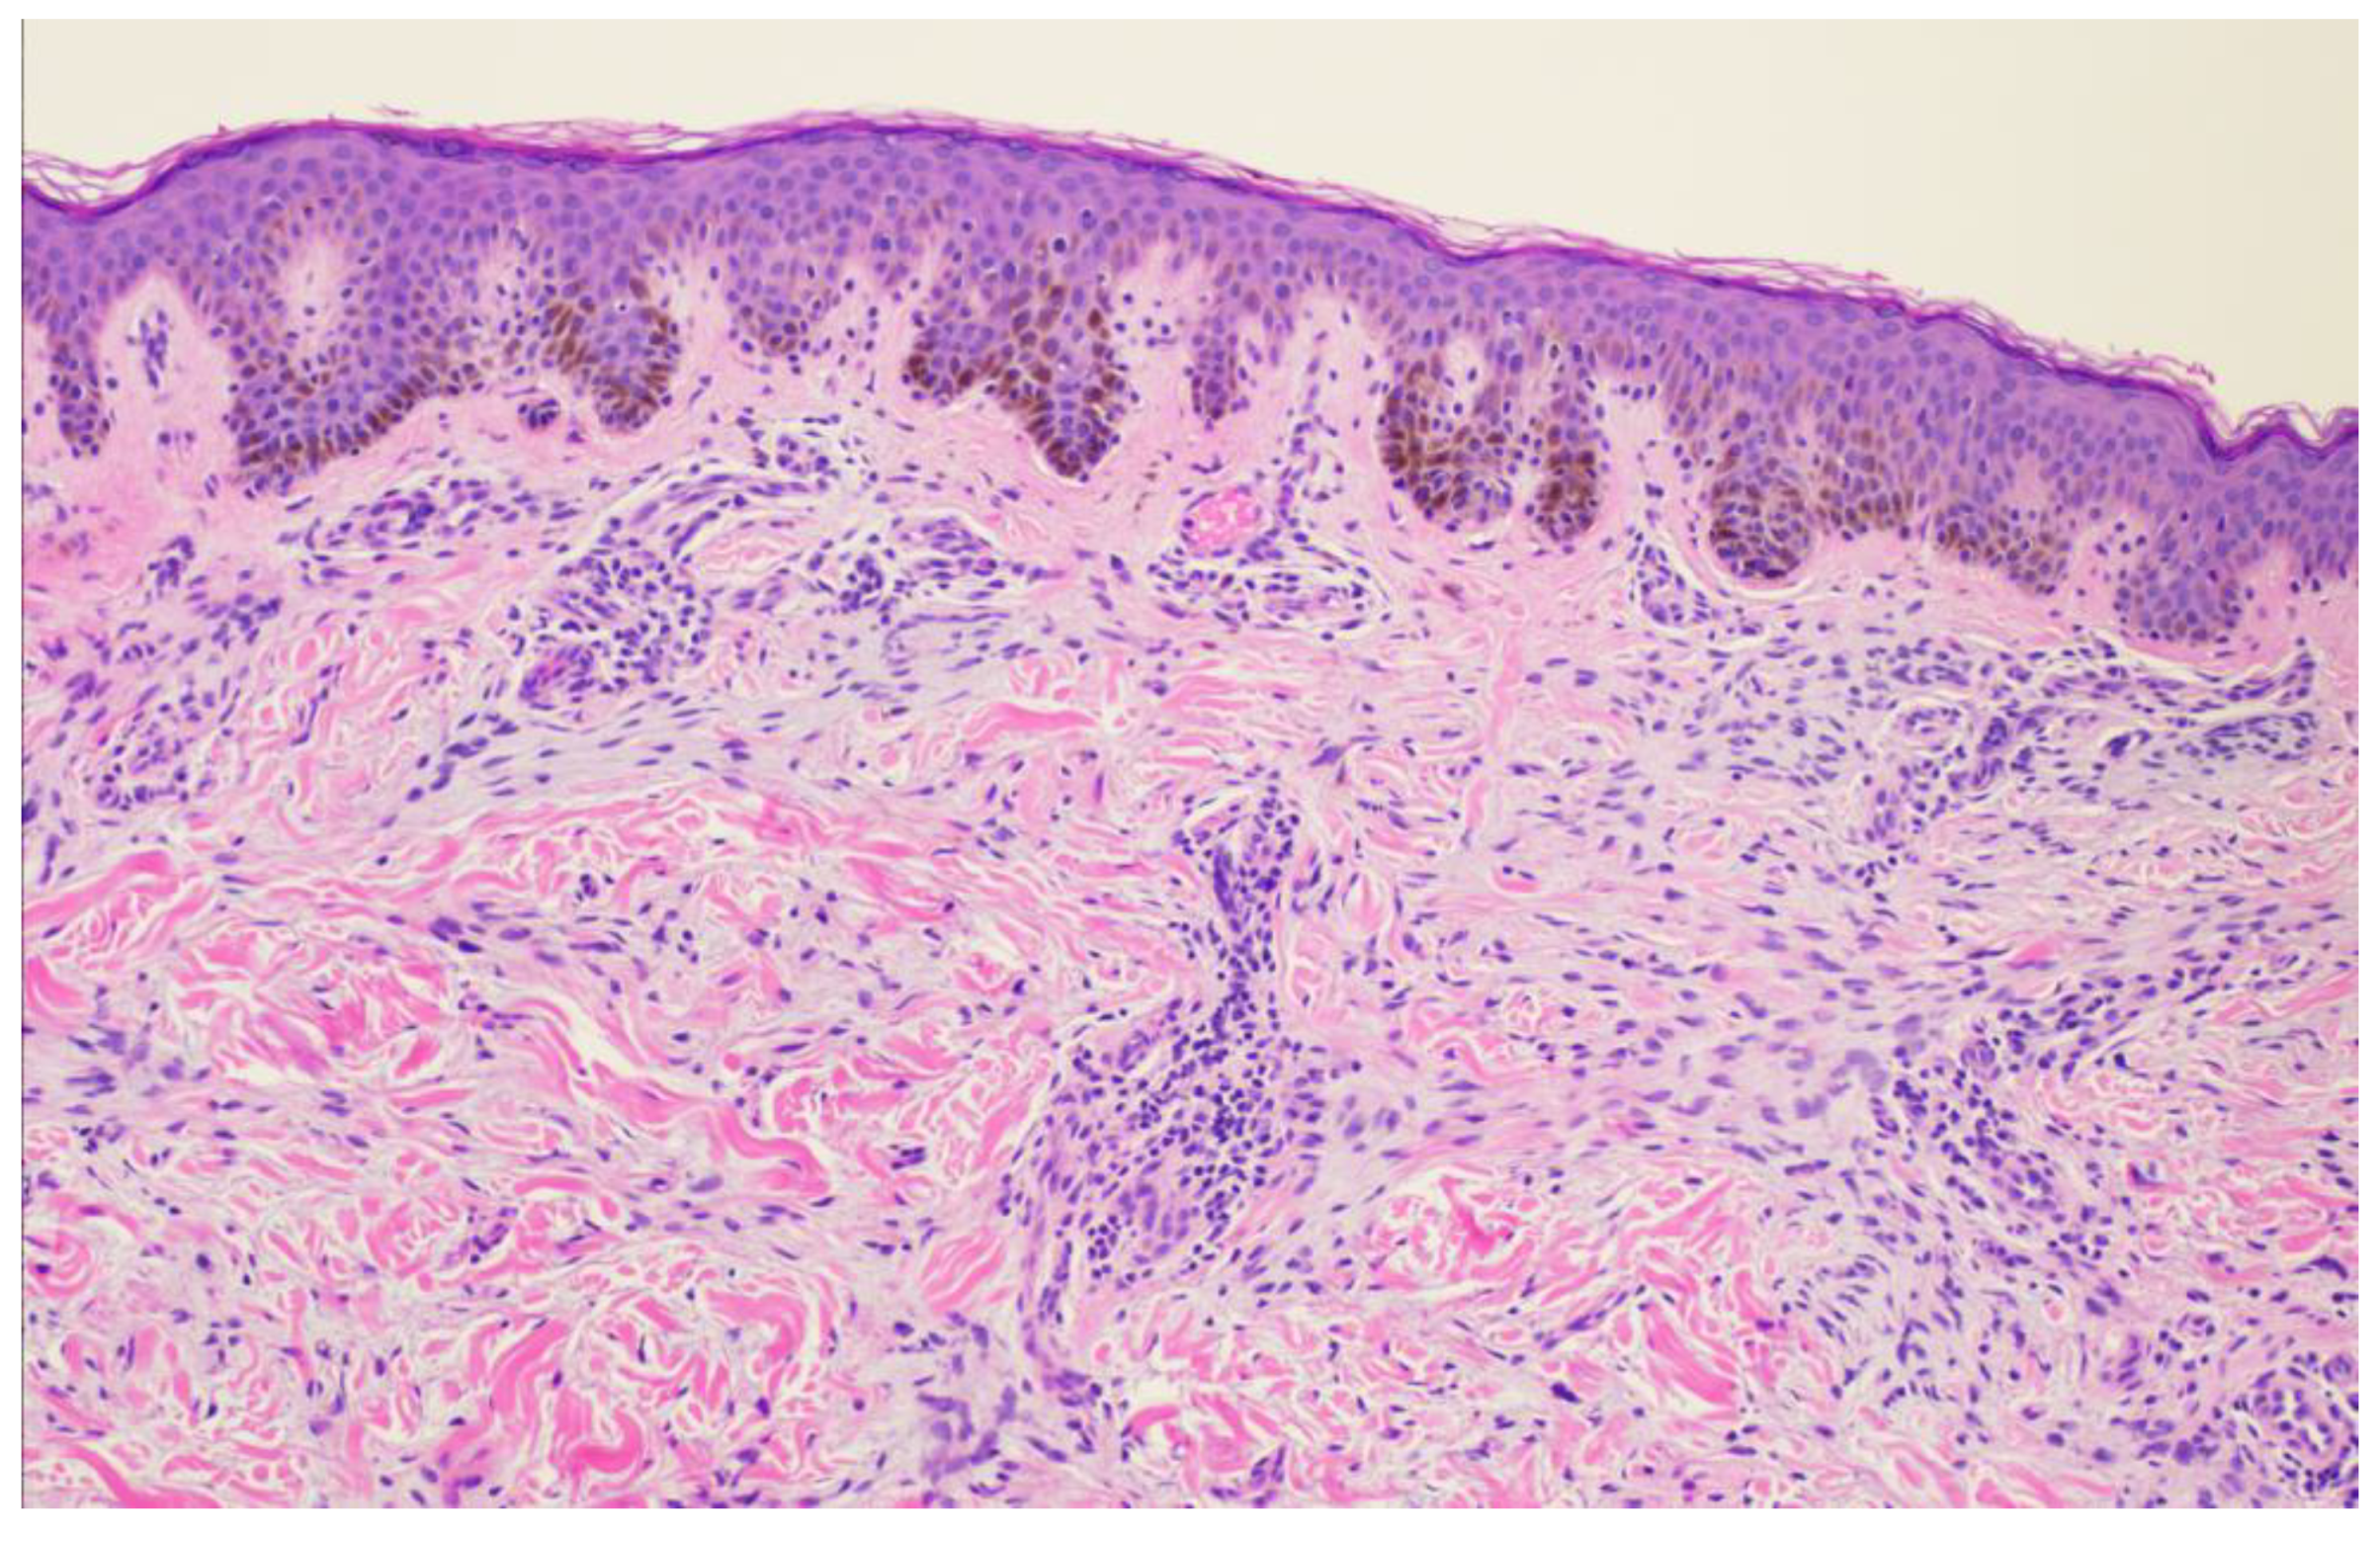

Figure 1). A punch biopsy was obtained and revealed atypical myxoid spindle cell neoplasm and involved margins with overlying mildly atypical compound melanocytic nevus. The specimen also displayed CD34 positivity (histopathology displayed in

Figure 2,

Figure 3,

Figure 4,

Figure 5,

Figure 6,

Figure 7,

Figure 8 and

Figure 9). A diagnosis of spindle cell lipoma was reached, and wide local excision with 2 cm margins was performed and subsequent pathology revealed clear margins.

Histopathologically, the presence of an atypical myxoid spindle cell neoplasm with CD34 positivity further complicated the diagnosis. The biopsy also revealed an overlying mildly atypical compound melanocytic nevus, which is an unusual finding in SCL and raised concerns about a potential collision tumor or a misdiagnosis.